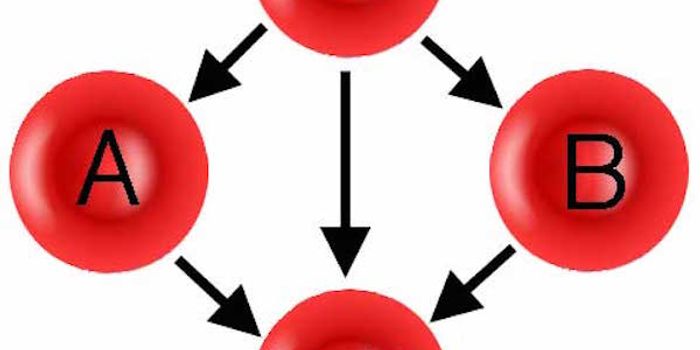

MAY 01, 2015ImmunologyThere are strict rules to blood transfusion. Only blood without A- or B-type antigens, such as type O, can be given to a ...